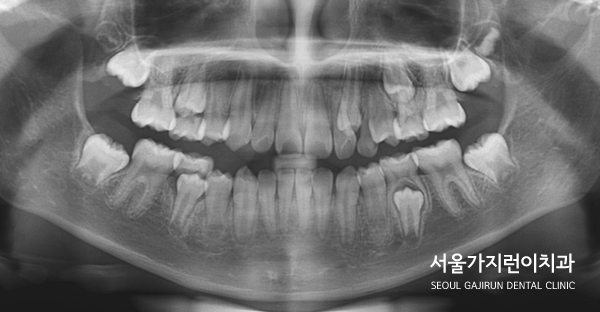

치열이 좁아서 공간이 부족하거나 유치가 제때 빠지지 않은 경우에는 '이소맹출'이 발생할 수 있었는데요. 치아의 맹출 방향 이상, 잇몸 혹은 뼈 내부의 병변, 유전적 및 발달적 용인에 의해 발생할 수 있었어요. 어린이 환자의 경우에는 이소맹출 때문에 좌측 유견치의 뿌리가 흡수되지 않았고 동요도 없는 상태였는데요. 골격적으로 봤을 때 하악골의 과성장 패턴도 보이고 있었어요.

그래서 엉뚱한 자리로 자란 상악 좌측 견치를 제 자리로 이동시키기 위해 잔존한 유견치를 발치했고 해당 자리로 이소 맹출된 견치를 이동시키는 플랜을 수립했었습니다. 어금니를 전방으로 이동시키면 견치를 배열할 공간이 줄어들 수 있었는데 환자의 보호자 분께서 미니스크류 사용을 반대하셨기 때문에 다른 방법을 찾아야 했었습니다. 그래서 환자 분의 경우 TPA(횡구개 아치)를 본딩해 어금니가 이동하지 않도록 잡아주었습니다.